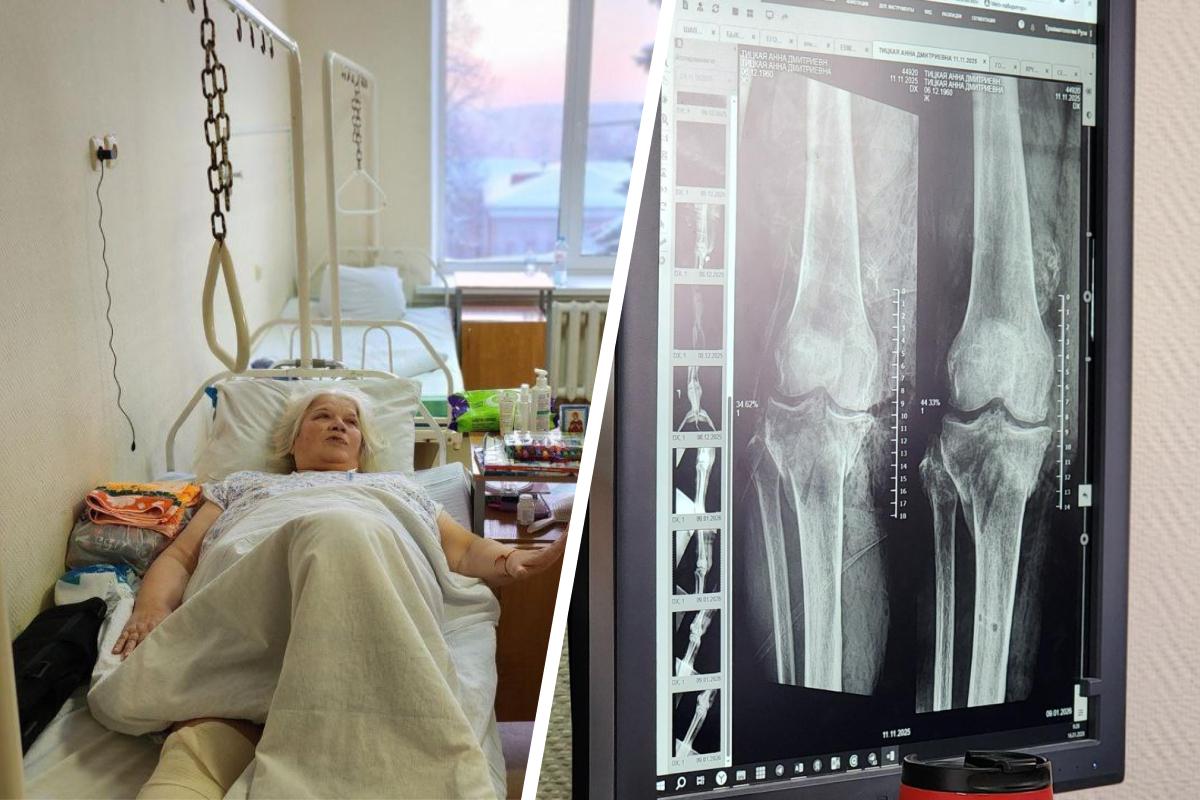

«64-летняя женщина была доставлена в больницу в тяжелом состоянии. Врачи диагностировали у нее открытый оскольчатый перелом обеих костей правой голени со смещением, обширную рваную рану подколенной области, а также множественные ушибы и ссадины», — рассказали в пресс-службе Минздрава Московской области.

Потерпевшую незамедлительно доставили в операционную, где медики выполнили срочное хирургическое вмешательство. Кости голени зафиксировали с помощью аппарата внешней фиксации.

«После подготовки раны была выполнена пересадка кожи, дефект мягких тканей закрыт. Перелом успешно срастался, сейчас аппарат уже снят, конечность зафиксирована ортезом», — добавили в ведомстве.